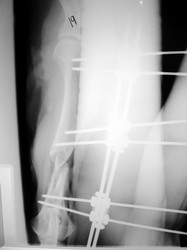

PRÁCTICAS CURSO DE FIJACIÓN EXTERNA PERFECCIONAMIENTO.

Húmero.